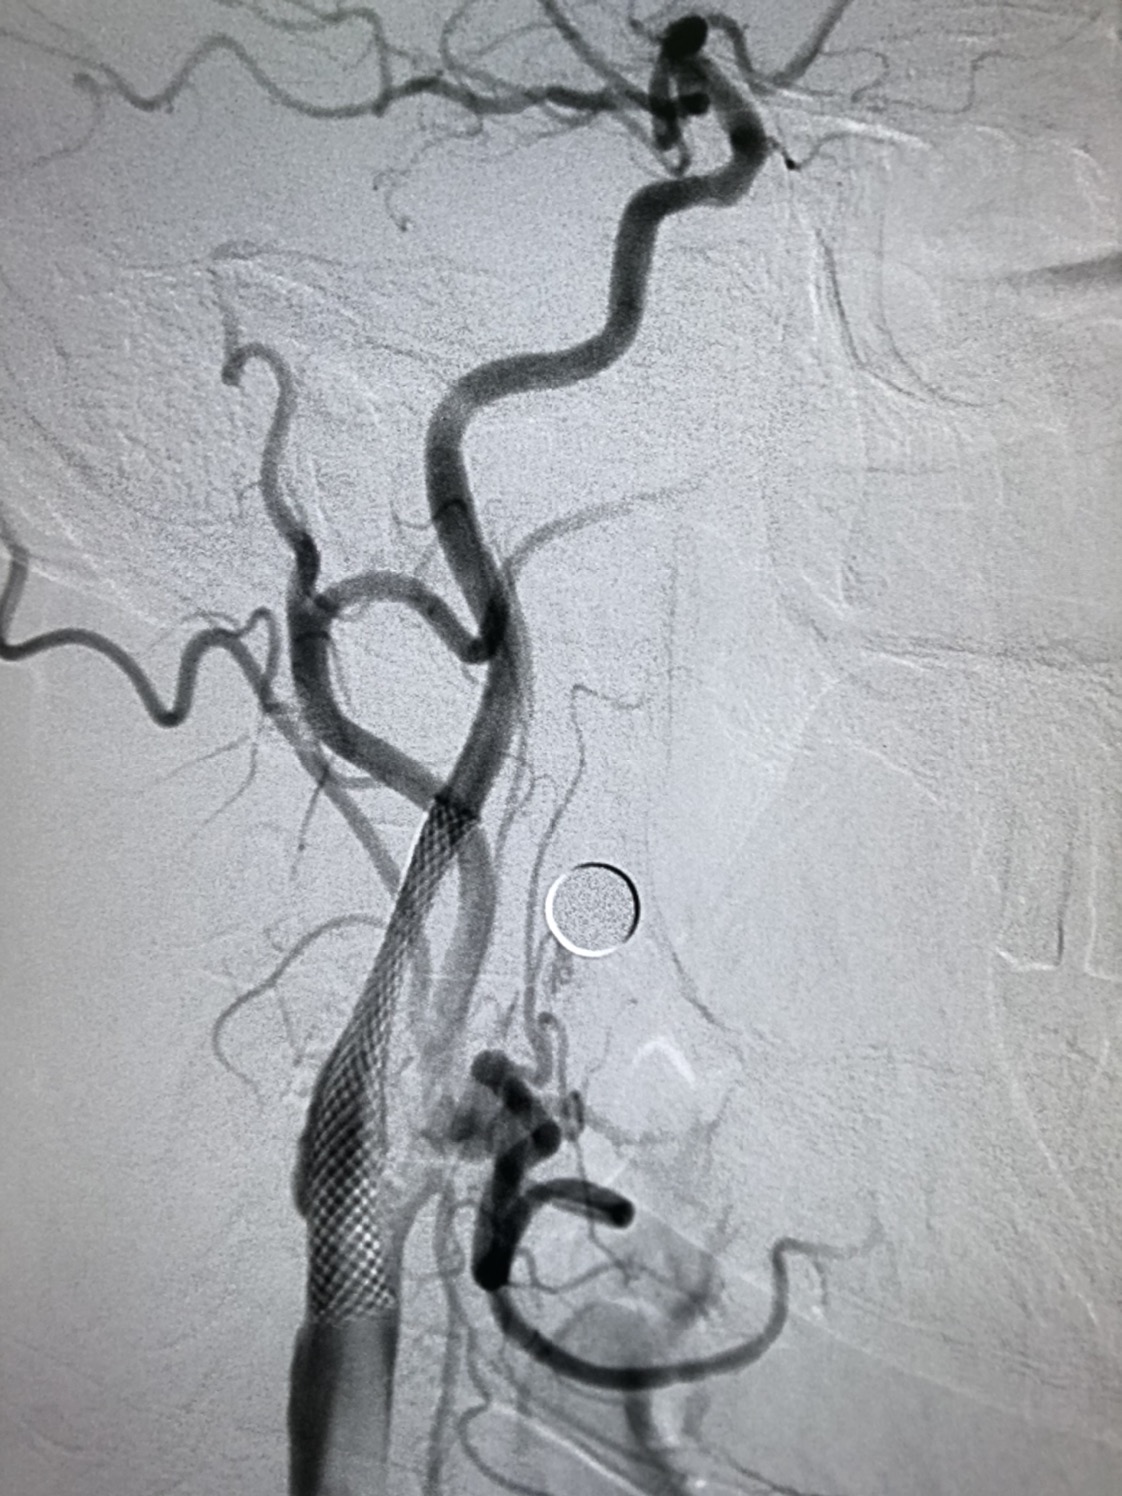

远端保护伞保护下,4/30球囊预扩后狭窄改善

WALLSTENT 9/40支架定位准确后释放

支架释放后狭窄解除

支架完全覆盖斑块,狭窄解除,支架形态柔顺贴合血管,无明显残余狭窄